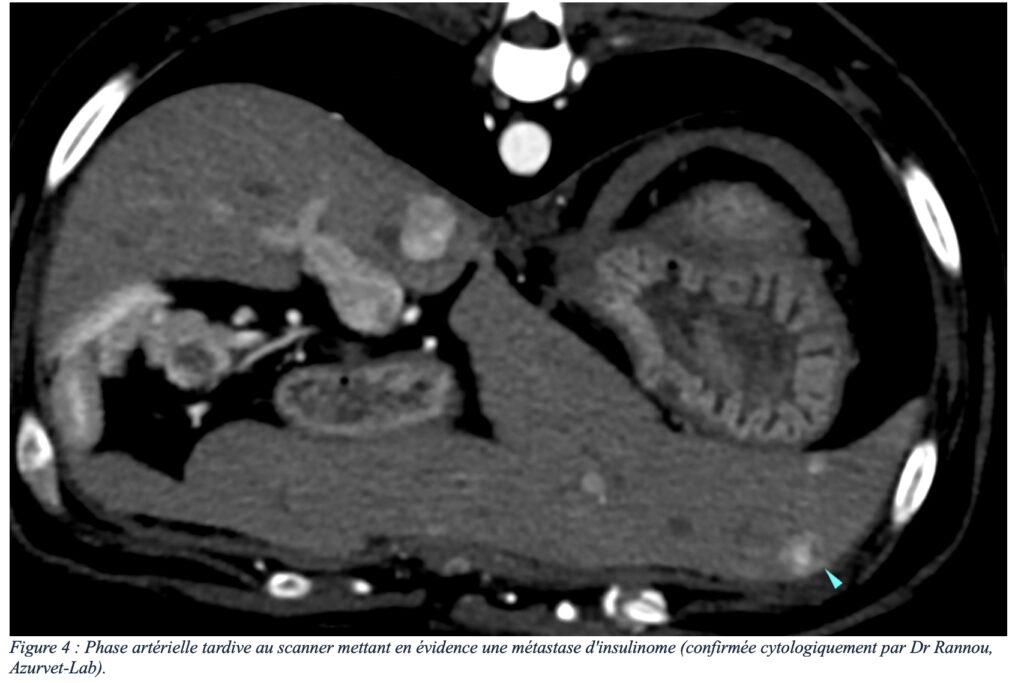

En tant que tumeur neuroendocrine, l’insulinome est quasiment systématiquement une tumeur maligne avec possibilité de dissémination métastatique. Les sites de métastases les plus fréquents sont les nœuds lymphatiques de drainage (notamment hépatiques, spléniques et coliques) et le foie. La présence de métastase est le seul critère pronostic négatif mis en évidence.

Le scanner, et plus particulièrement la phase artérielle tardive d’un angioscanner (3) (figure 2), est un examen présentant une sensibilité nettement supérieure à l’échographie (4). En effet, les insulinomes et leurs métastases présentent un rehaussement intense et précoce après injection intraveineuse de contraste iodé, permettant une détection plus fiable des insulinomes et leurs éventuelles métastases (bien que des faux positifs soient possibles), tout en s’affranchissant des limites liées au gabarit de l’animal (figures 3 et 4). Les angioscanners peuvent être effectués manuellement, mais les injecteurs automatiques de contraste facilitent la partie technique de cet examen (figure 5).